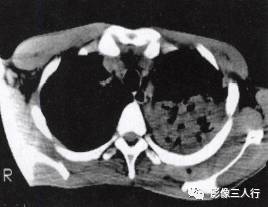

胸部影像常呈肺段或肺叶急性炎性实变。影像实变期表现为密度均匀的致密影,在实变 区中可见空气支气管征。其病理基础是由于广泛的肺泡腔内炎性渗出,肺充气明显减少,使 正常充气的各级支气管与实变的肺泡构成鲜明的对比,形成支气管充气征。见图4至图6。 医学百科网 | YxBaike.Com